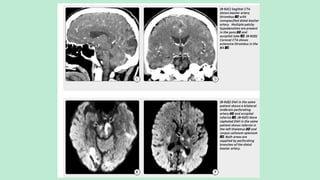

CEREBRAL GAS EMBOLISM

Causes include:

1. IV catheter

2. CV line

3. Lung biopsy

4. Craniotomy

5. Decompression sickness

6. Hydrogen peroxide ingestion

IMAGING FEATURES OF CEREBRAL GAS

EMBOLISM

Asymptomatic air following intravenous catheter placement is most

commonly observed as an incidental finding, typically as dots of air in the

cavernous sinus.

Intracranial air bubbles can be identified in 70% of symptomatic CGE cases,

appearing on NECT as transient small intravascular rounded or curvilinear

hypodensities, typically located at the depths of sulci.

Intraparenchymal air is less common.

Air is quickly absorbed and can rapidly disappear. If massive air embolism

occurs, cerebral ischemia or diffuse brain swelling typically ensues.